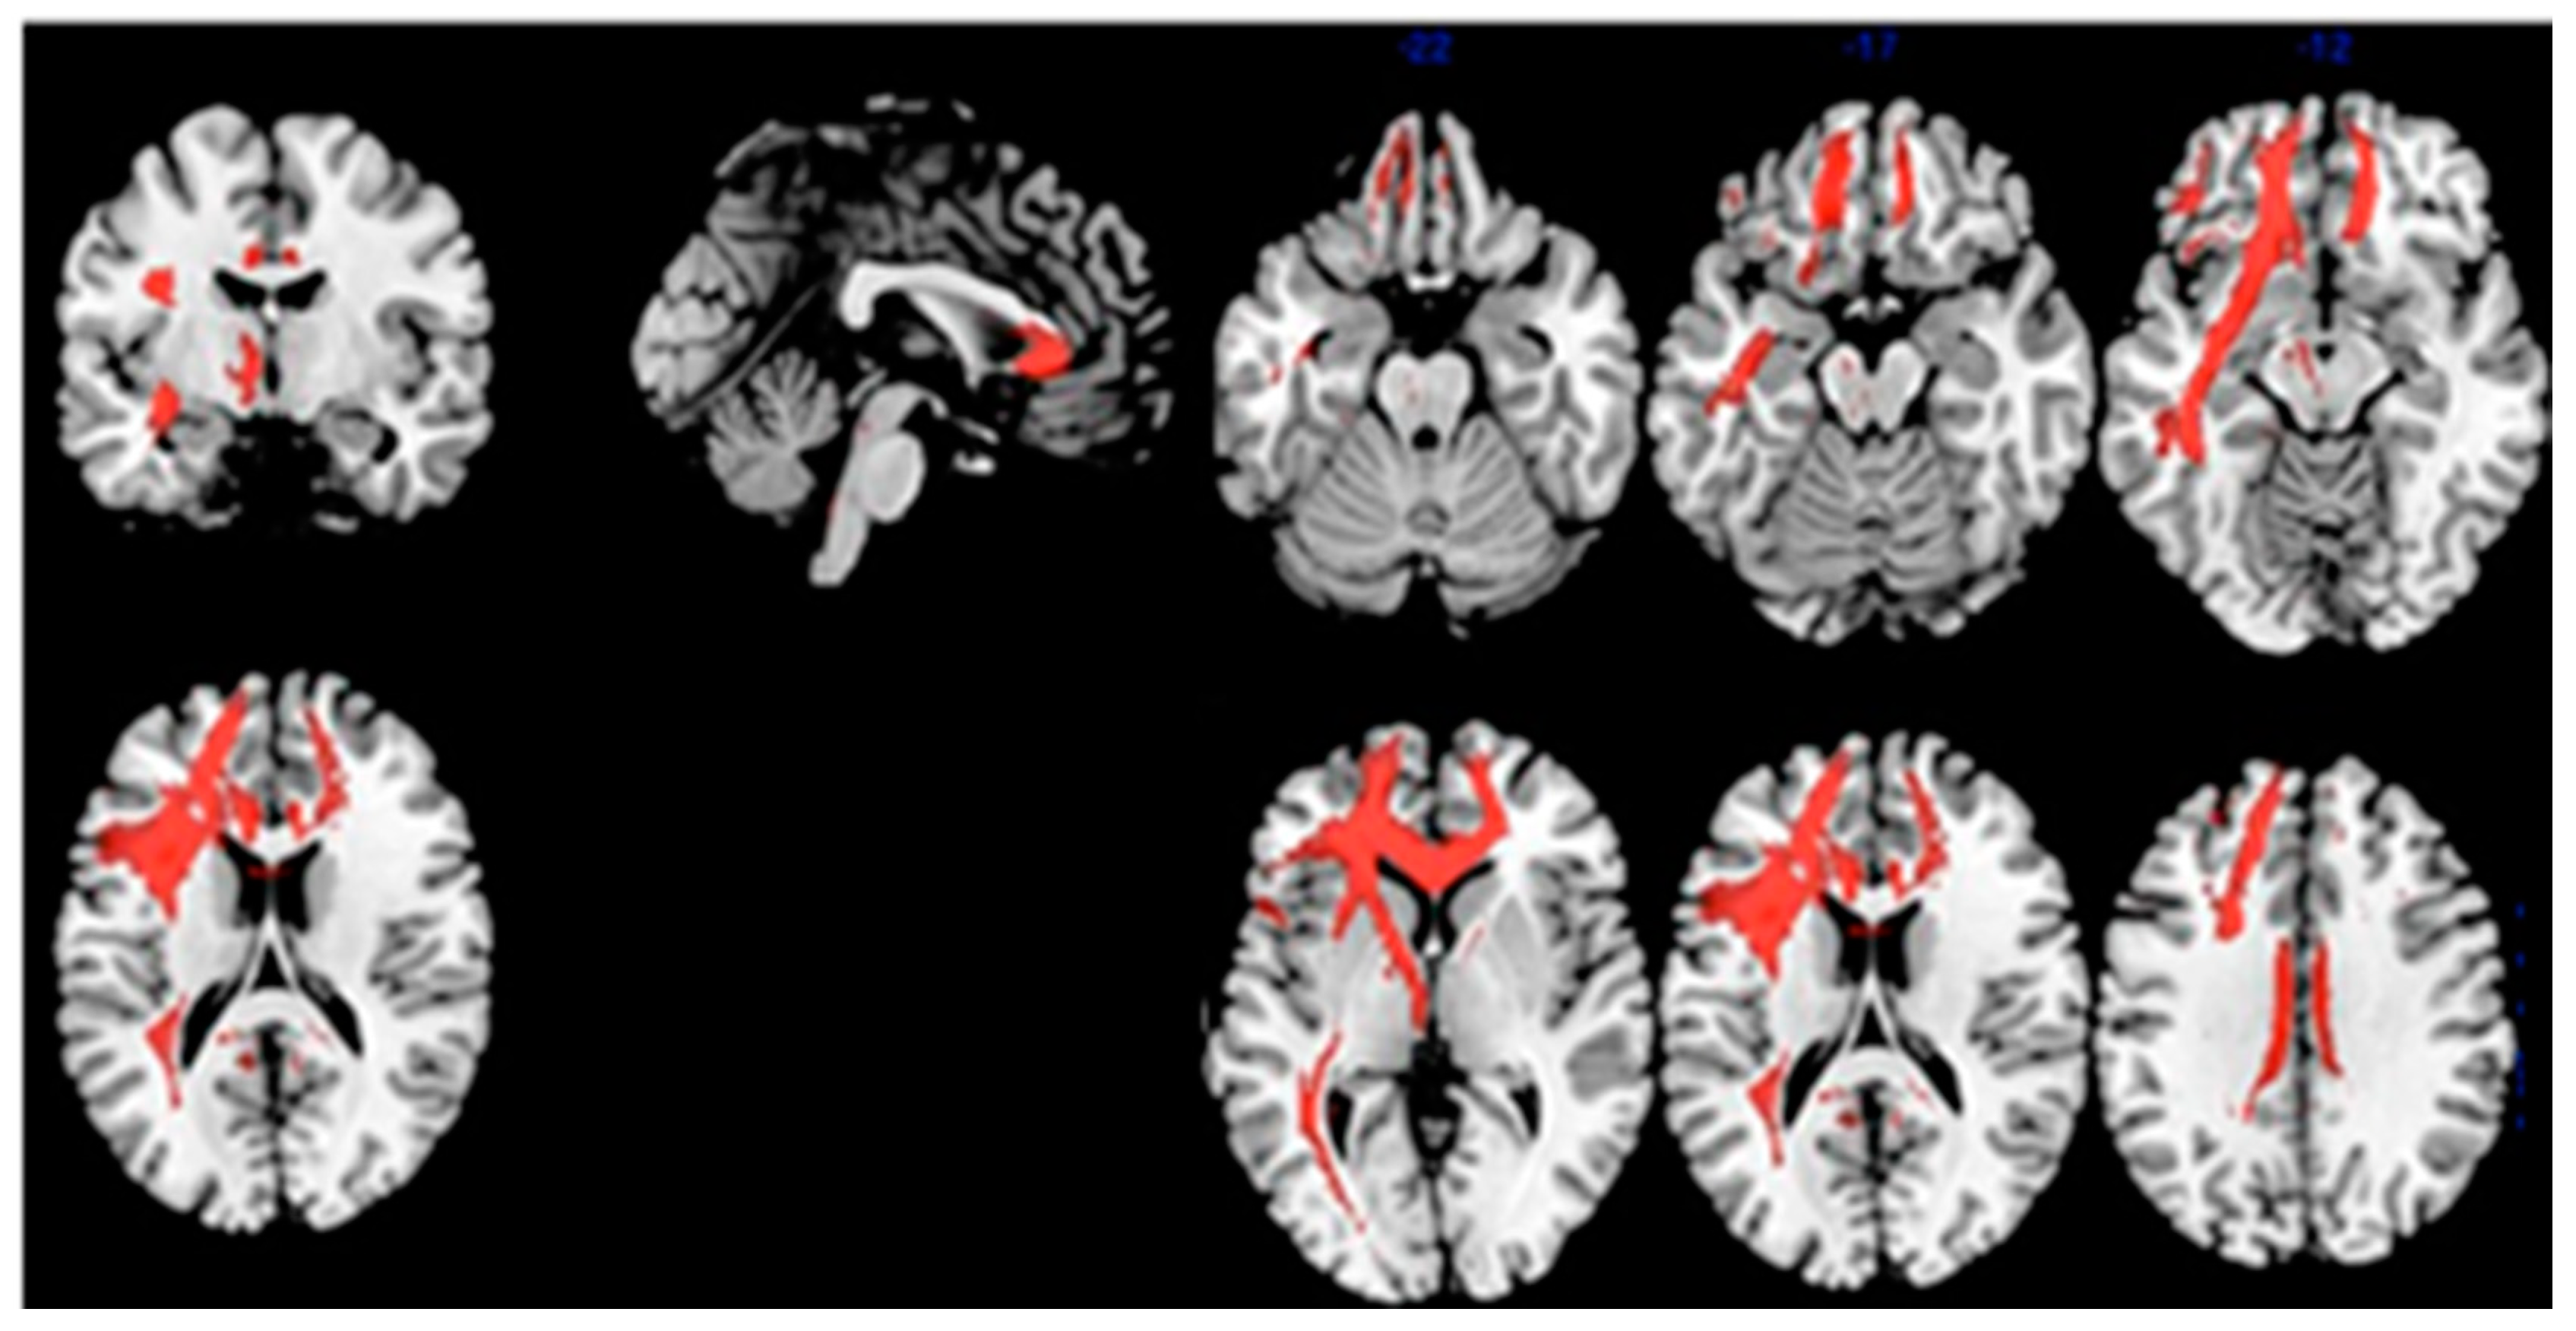

| Statistic | Cluster Level | Voxel Level | |||||

|---|---|---|---|---|---|---|---|

| Cluster Extent | FWE-Corr. p Value | Cortical Region | Z Score of Maximum | Talairach Coordinates | Cortical Region | BA | |

| Comparison: Brain metabolism HC vs. MCI-AD | 2191 | 0.000 | L Parietal | 5.47 | −48, −68, 52 | Inf. Parietal Lobule | 39 |

| 2189 | 0.000 | R Parietal | 5.05 | 48, −54, 44 | Inf. Parietal Lobule | 40 | |

| 1458 | 0.000 | L Parietal | 4.85 | −12, −46, 38 | Precuneus | 31 | |

| 1295 | 0.001 | L Temporal | 4.22 | −72, −26, 4 | Middle Temp gy. | 21 | |

| Correlation: Index of Sensitivity of Cueing (ISC)–brain metabolism in MCI-AD | 2481 | 0.002 | L Frontal | 4.96 | −14, 44, 0 | Anterior Cingulate | 32 |

| L Frontal | 4.45 | −22, 44, 28 | Sup. Front. Gy. | 9 | |||

| L Frontal | 4.38 | −18, 52, 18 | Sup. Front. Gy. | 10 | |||